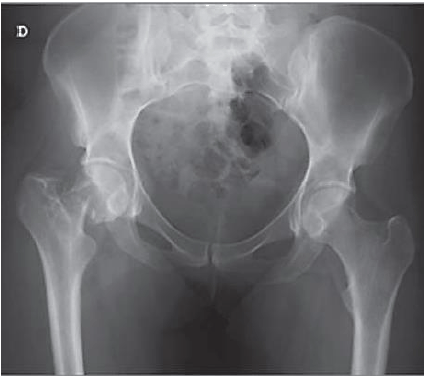

Classificamos a fratura abaixo como:

A imagem abaixo se refere a: